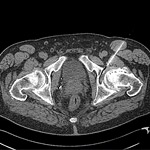

Διαδερμική εμφύτευση βλαστικών κυττάρων, με βελόνη καθοδηγούμενη από αξονικό τομογράφο.